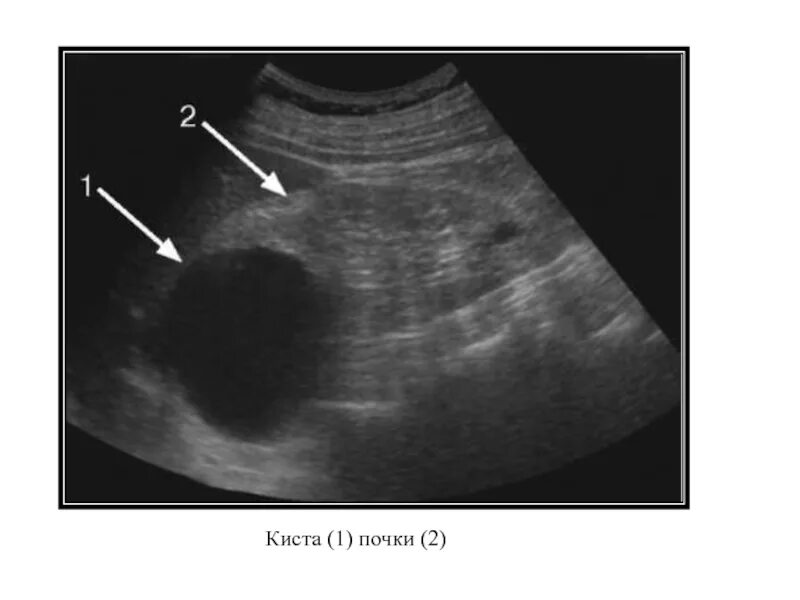

Можно ли вылечить кисту почки